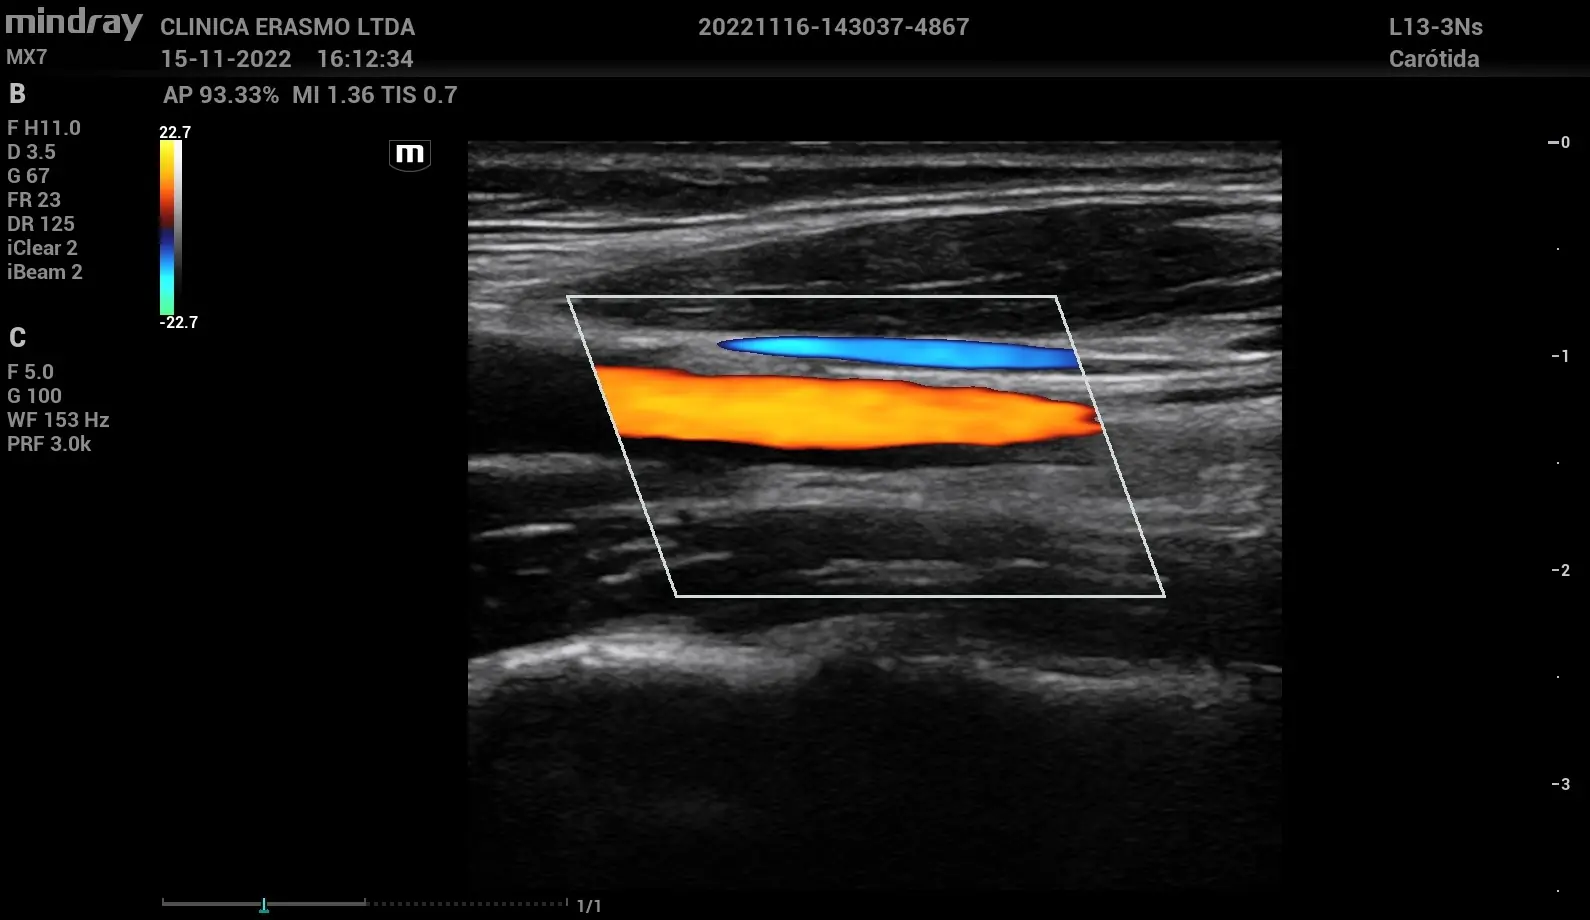

- Doppler color: representa el flujo sanguíneo en tiempo real mediante un mapeo codificado por colores, facilitando la identificación visual de turbulencias, flujos retrógrados o alteraciones hemodinámicas. Es clave en estudios de válvulas y comunicación interventricular.

Doppler color y su aporte al análisis del flujo sanguíneo

Al superponerse sobre la imagen bidimensional, el doppler color proporciona una visión integrada de la anatomía y la dinámica del flujo, lo que mejora considerablemente la eficiencia diagnóstica y permite una mejor orientación de las muestras en estudios posteriores con doppler pulsado o continuo.

- La identificación de estenosis y zonas de alta velocidad: mediante el patrón colorido del flujo turbulento, se puede ubicar el punto exacto de una estenosis o estrechamiento vascular, como ocurre en valvulopatías o coartación aórtica.

- La detección de flujo turbulento en aneurismas o disecciones: en estructuras vasculares dilatadas o lesionadas, el doppler color evidencia patrones irregulares de flujo que orientan el diagnóstico.